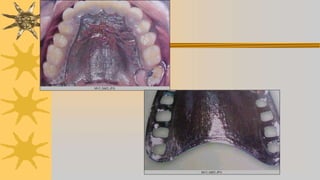

RECEPCION E INSPECCIÓN DE

PROTESIS

Debe observarse :

Que la estructura metálica este bien acabada, pulida sin

aristas

Que parte acrílica, sus bordes que sigan sinuosidad de

encia, redondeado

Que parte interna no tenga rugosidades o perlas, pero no

retocar

Caras externas de base, lisas

Control de estructura colada

Verificar trayectoria de inseción y remosión

Si hay resistencia buscar zona

Apoyos oclusales asentados completamente sobre descansos

oclusales

Bases asentadas sobre rebordes

No debe bascular ni generar isquemia

Pruebas fonéticas, 48 horas después de ionstalada PPR